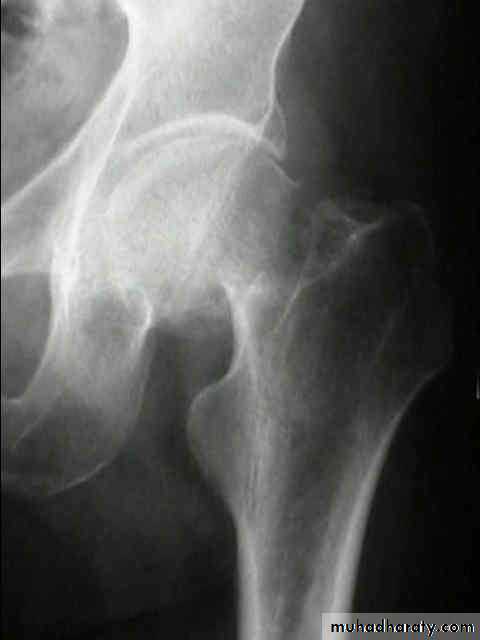

:Radiological classification

GRADE 1

:the femoral head is in its normal position or tilted into valgus and impacted on the femoral stump.

GRADE 3

The femoral head tilted out of position and the trabecular marking are not in line with those of innominate bone.

Lower limbs

GRADE 4

The femoral head trabeculae are normally aligned with those of innominate bone.